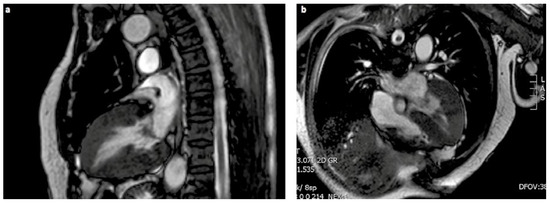

50 Years of Heart Transplantation

by Marko Turina

Cardiovasc. Med. 2018, 21(9), 209; https://doi.org/10.4414/cvm.2018.00583 - 19 Sep 2018

Abstract

Heart transplantation has made tremendous progress since its first clinical use in 1968 and has enabled survival of many patients with intractable heart failure. A pioneer of the Swiss heart transplant programme looks back. Full article

Show Figures

Figure 1